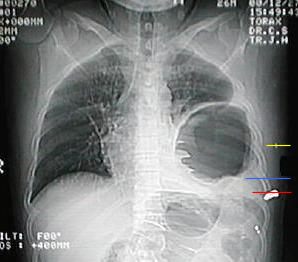

• Al observar los estudios radiológicos de Rx. PA y L Izq. del tórax, se decide su hospitalización y realizar estudios pertinentes por la sospecha de una Hernia Diafragmatica Izquierda.

Rx. Tórax al momento de su Ingreso. motivo de su referencia a nuestro hospital.